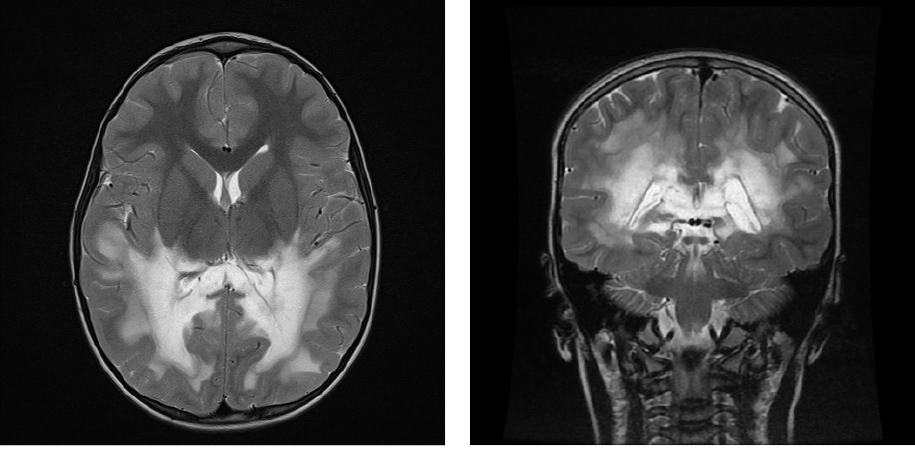

MRI with gadolinium contrast revealed white matter lesions suggestive of X-ALD, assessed as 16 of 34 on the Loes scale (Image 1). The electroencephalogram (EEG) revealed generalised epileptic activity without seizures. An unspecified impairment in learning was detected. The skin was darker in the areas of knees and fingers, and laboratory tests confirmed primary adrenal insufficiency (cortisol 90.82 nmol/l; cf. normal range: 177–578 nmol/l, renin 23.3 ng/ml; cf. normal range: 1.6–14.7 ng/ml, ACTH 194.6 pmol/l; cf. normal range: < 14.15 pmol/l).

Biochemical tests showed an elevated concentration of VLCFA, with levels of C26:0 at 2.9 nmol/ml (normal range: 0.2–1.6), C26:0 and C22:0 ratio 0.077, (normal range: 0.005–0.029), C24:0 and C22:0 ratio 1.84 (normal range: 0.55–1.05). A hemizygous, potentially pathogenic mutation in the ABCD1 gene was confirmed.

Based on MRI images that showed lesions of >9 points on the Loes score, and, considering neurological impairment as 7 out of 25 on the neurologic function scale, it has been determined that the patient’s X-ALD stage was advanced. The consensus during the medical consultation was to not initiate treatment with allogeneic HSCT because the procedure could worsen the neurological impairment and significantly impact the patient’s quality of life. If allogeneic HSCT is performed, it would cause a prolonged hospitalisation period and a high likelihood of complications, such as central blindness and deafness, impairment of perception and mobility, and the development of GvHD.